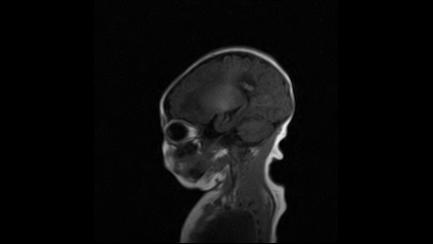

标题: PED3413:患儿女6天体检

缺血缺氧性脑病

6天为新生儿,髓鞘发育正常;左侧颞顶叶蛛网膜下腔增宽,请结合临床。

1。缺血缺氧性脑病2。左侧颞顶叶外部性脑积水,可观察

半卵圆中心上方层上可见对和乐大脑皮质t1高信号,考虑有hie可能,不知有何症状,建议加做dwi及复查

符合缺氧缺血性脑病影像表现。